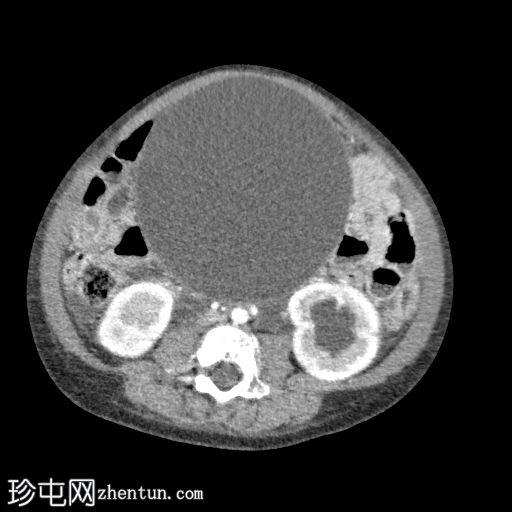

轴位增强扫描(门静脉期)

膀胱颈下部可见一异质性强化软组织肿块,导致膀胱出口梗阻和膀胱明显囊性扩张(头尾长:19厘米)。

肿块前方与耻骨联合相邻,位于Retzius间隙内;后方与直肠和乙状结肠相邻;虽然脂肪间隙模糊,但未见明确的侵犯。

双侧输尿管肾积水,继发于膀胱出口梗阻。

CT未见明显淋巴结肿大。